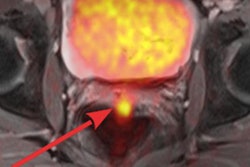

The 3D MR image offers a horizontal view across the cervical canal and reveals encircling fibers, which give support to the fetus and prevent it from entering the birth canal too soon. Image courtesy of the University of Leeds.Approximately 25% of miscarriages that occur during the fourth to sixth month of a pregnancy happen because of a weakened cervix. High-resolution 3D DTI-MR images thus far have provided details of the microstructure of the organ, which could explain why certain women have pregnancy issues, said lead author James Nott, an anatomy demonstrator and doctoral candidate at the university's Faculty of Medicine and Health.

In this study, 3D DTI-MR images evaluated cervical tissue based on water content to discover a fibrous structure that extends along the upper part of the cervix, with fibers that are much more visible at the point where the cervix attaches to the womb.

During pregnancy, the fibers provide a strong supporting barrier that keeps the fetus and amniotic sac in place to preventing micro-organisms from entering the uterus. MRI scans show these supporting fibers are less prominent further down the cervix as it joins the birth canal.